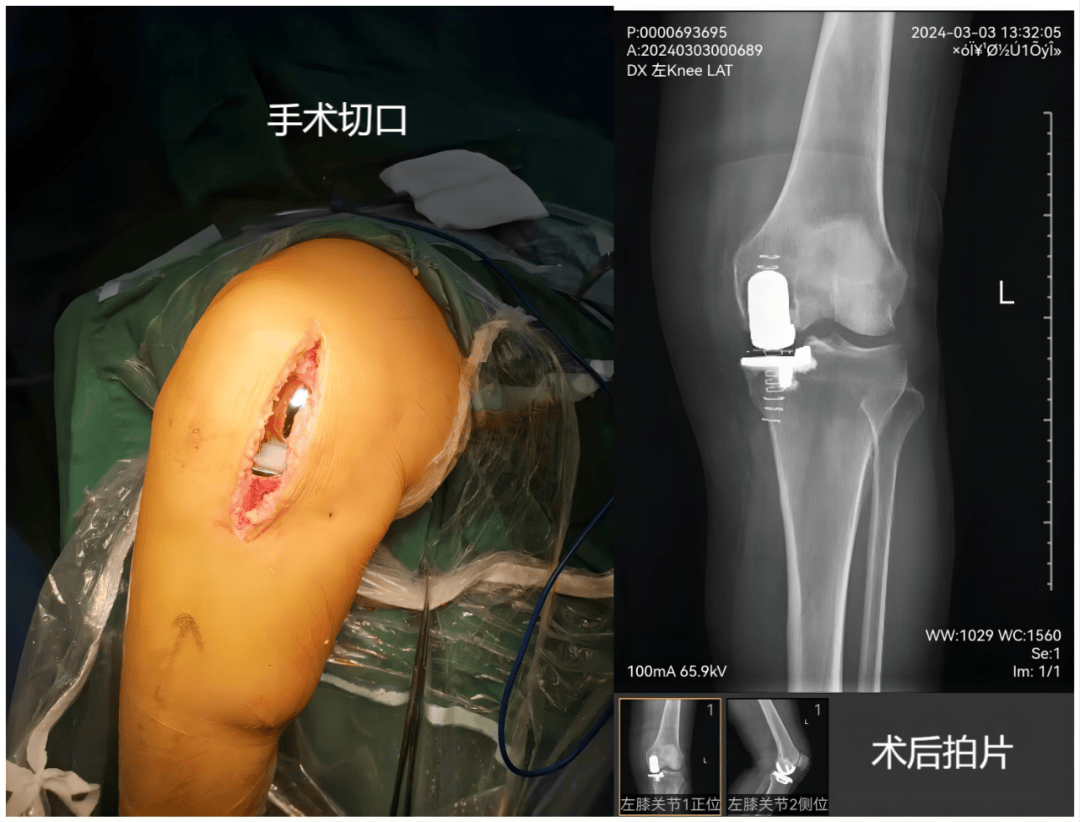

2、全膝关节置换手术是用人工生物材料置换已被破坏的膝关节骨和软骨,切除磨损破坏的关节面并植入人工关节,以解除疼痛恢复关节功能提高生活质量的外科手术 以下从手术背景适用人群手术好处三方面展开介绍手术背景膝关节是人体最易损伤和老化的部位之一,中年以后,其组织结构发生退行性变,滑液分泌减。

7、膝关节置换术,全称膝关节表面置换术,是一种通过手术将受损膝关节表面用人工材料替换的治疗方法手术目的与适应症该手术主要用于治疗终末期膝关节炎膝关节畸形等严重膝关节疾病当膝关节因骨性关节炎类风湿性关节炎创伤性关节炎等疾病,导致关节面磨损缺失,出现剧烈疼痛活动受限关节畸形等。

10、膝关节置换术是一种通过手术将受损的膝关节表面替换为人工假体的外科手术,主要用于治疗严重的膝关节疾病其核心目的是缓解疼痛矫正畸形并恢复膝关节功能,从而提升患者生活质量手术适应证手术适用于因膝关节骨关节炎类风湿关节炎等疾病导致严重疼痛畸形或功能障碍的患者年龄方面,6080岁患者为。

11、膝关节置换手术,又称膝关节成形术,是通过使用人工关节假体替换受损膝关节部分,以恢复功能缓解疼痛和改善生活质量的外科手术该手术主要针对保守治疗无效的严重膝关节疾病患者,其核心要点如下一核心定义与治疗目标手术通过切除病变的关节软骨骨质及周围软组织,植入金属高分子聚乙烯等材料制成的。

13、全膝关节置换术是一种通过外科手术,将病损的膝关节部分或全部用人工关节假体替代的治疗方式它主要针对严重膝关节疾病,当保守治疗无法有效缓解症状改善膝关节功能时采用该手术旨在减轻患者疼痛矫正畸形恢复和改善膝关节运动功能,从而提高患者生活质量适用人群方面,年龄通常建议在60 80岁,但。

15、膝关节置换术是将受损膝关节部分或全部替换为人工关节的外科手术,旨在缓解疼痛改善关节功能手术适应证 严重膝关节骨关节炎因软骨磨损骨质增生导致疼痛和功能障碍,保守治疗无效时适用例如,患者长期行走困难上下楼梯疼痛剧烈,严重影响日常生活类风湿关节炎晚期患者膝关节严重破坏畸形且功能。